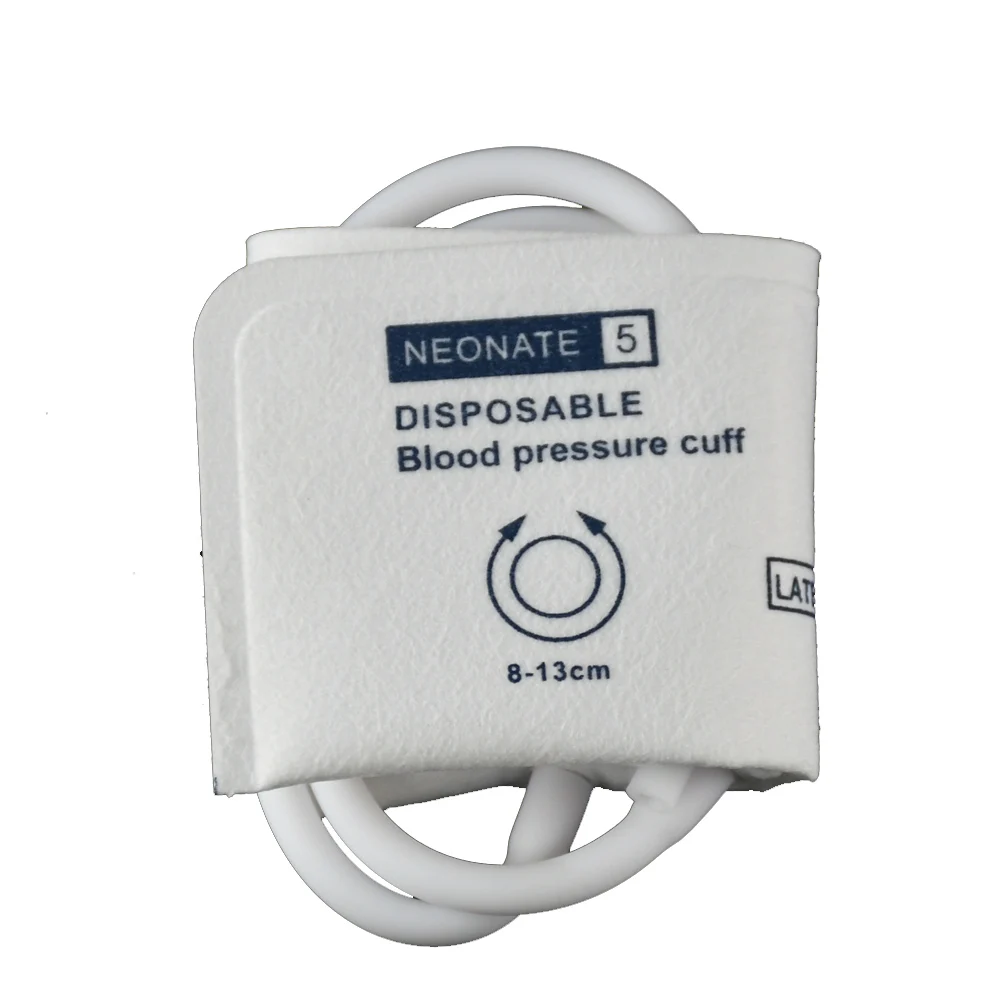

Одноразовый двойной брикет NIBP, медицинский наручный манжет, для цифрового монитора артериального давления, прибор для измерения артериаль...

aliexpress.com